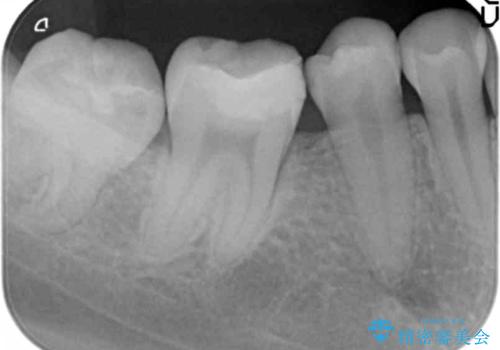

欠けた詰め物をすべて取り除くと深いところに取り残された虫歯を発見しました。

虫歯の除去後は残った歯の厚みが薄くなっていたため、今後の破折リスクを考慮してクラウンでの修復処置となりました。

虫歯が深く歯の神経の炎症が予想される箇所には鎮静作用のあるセメントを敷き、経過をみた後に被せ物をセットしました。

写真・レントゲン画像からもわかる通り、適合の良いクラウンを入れることができました。